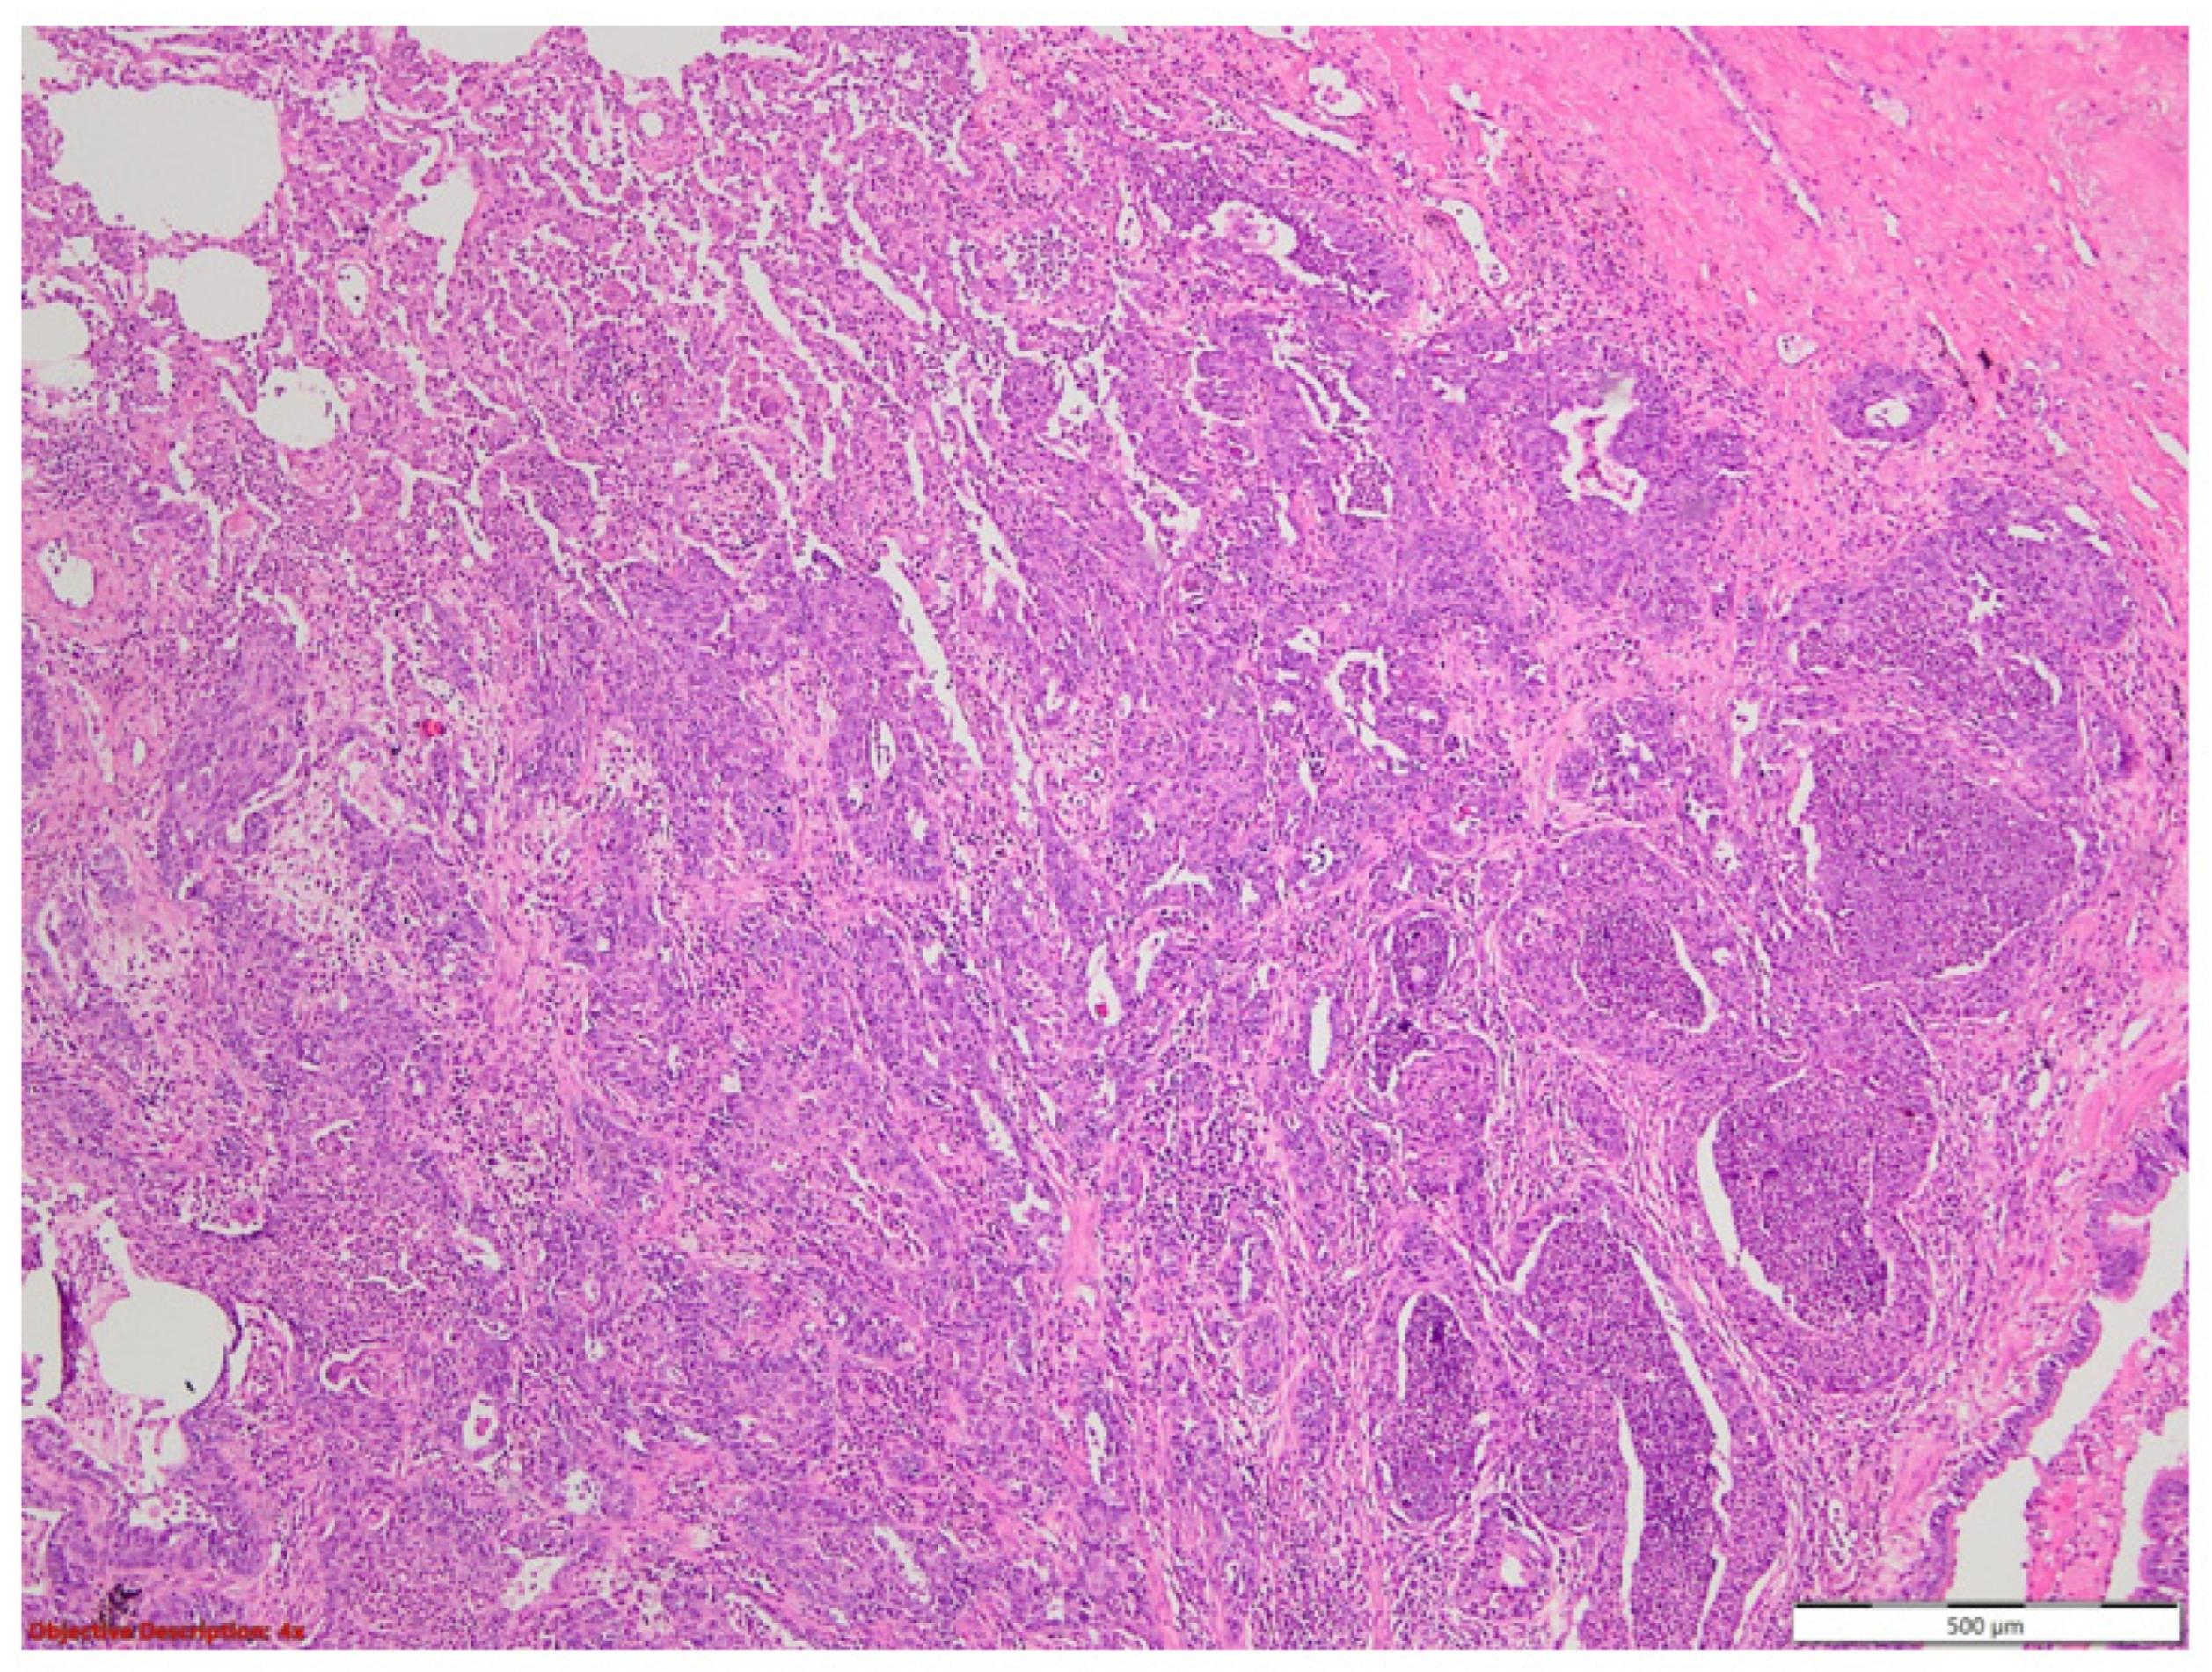

3.1. Case No. 1

3.2. Case No. 2

3.3. Case No. 3

3.4. Case No. 4